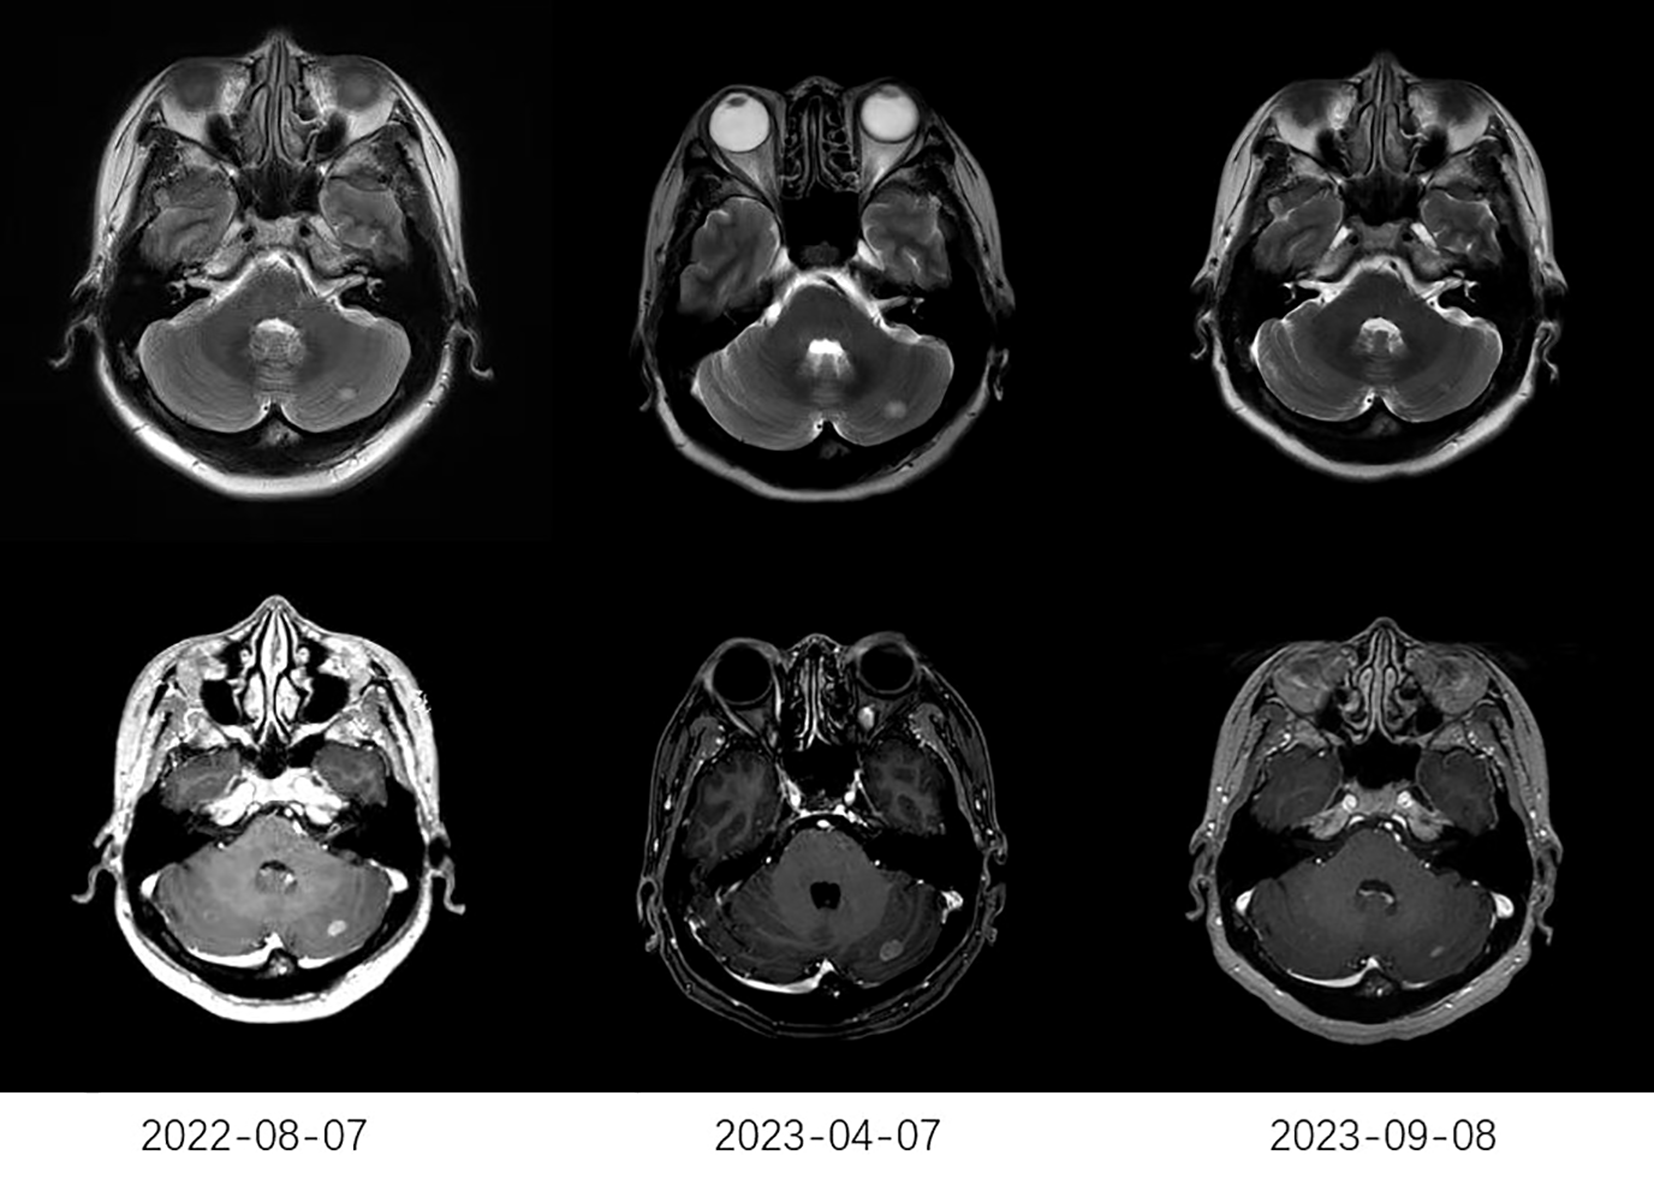

The treatment response to anlotinib is summarized in Table 2. The median CNS PFS of 29 patients was 7.2 months (95% confidence interval [CI], 3.5-10.9 months; Figure 1A), and the median OS was 10.2 months (95% CI, 5.6-14.8 months; Figure 1B). Systemic ORR and DCR were 34.5% and 82.8%, respectively. Among the 29 patients, 1 achieved an iCR, 8 achieved an iPR, 16 had iSD, and 4 had iPD, with an iORR of 31.0% and an iDCR of 86.2%. In addition, Among 16 patients who had iSD, 9 patients had multiple BMs, 7 patients had single BM, 2 patients had received prior antinagiogenic therapies. Among 8 patients who had iPR, 3 patients had multiple BMs, 5 patients had single BM, 1 patient had received prior antinagiogenic therapies. The patient with iCR had multiple BMs and had not received prior antinagiogenic therapies. Figure 2 shows the typical and clear magnetic resonance imaging (MRI) images of one patient before and after the administration of anlotinib. This patient has never been previously submitted to CNS radiotheraphy treatment.

Figure 2

The typical MRI images of one patient. The MRI on April 7, 2023, showed a larger lesion than that on August 7, 2022. After receiving anlotinib (2023-09-08), MRI showed a significant reduction in the lesion compared to that before receiving anlotinib (2023-04-07). MRI, typical magnetic resonance imaging.